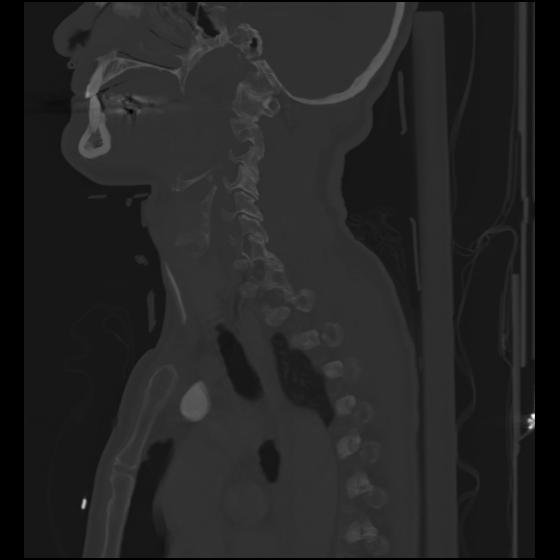

24 ANGIO,CE,Sag-MIP,5.000,ANGIO,Sag-MIP,